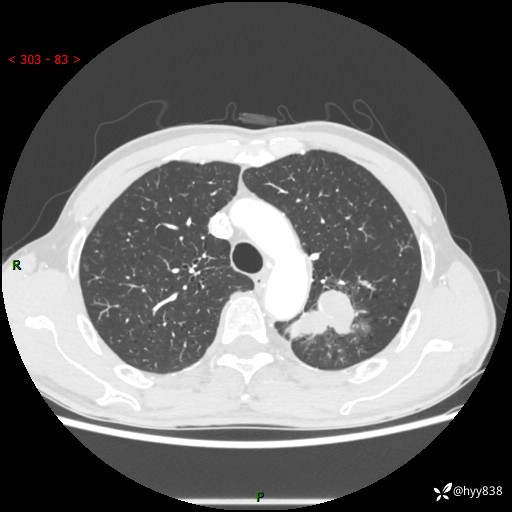

老年男性,咳嗽咳痰伴痰中带血4月。沿支气管铸形生长的不多---结果公布~

现病史:患者余4月前发现咳嗽咳痰伴痰中带血,无胸闷、胸痛、头晕、恶心、呕吐等不适,2天前因体检发现肺部结节遂于当地市第一人民医院行胸部CT薄层平扫+三维重建示:1.左肺上叶尖后段占位性病变考虑肿瘤性病变伴阻塞性肺炎,右肺上叶后段磨玻璃结节。2.肝内多发囊性灶、左肾结石。现患者为求进一步治疗,于我院门诊就诊,门诊以“肺结节”收入院。 自患病以来,精神、饮食、睡眠尚可,大小便正常,体力体重无明显减轻。

胸部CT增强扫描(外院平扫)